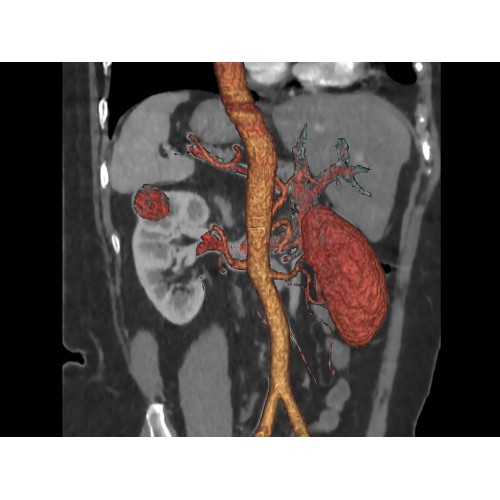

• Высокое качество изображения благодаря усовершенствованной системе реконструкции данных.

• Сниженная лучевая нагрузка на пациента без потери информативности снимков.

• Широкая область применения: от неврологии до кардиологии и онкологии.

• 3D-реконструкция костных структур для планирования операций.